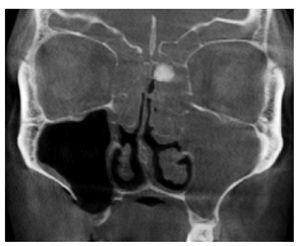

Figura 4. Tomografía volumétrica digital dental: plano coronal.

En la TVD se observa un seno maxilar izquierdo íntegro y homogéneamente ocupado, además de una obstrucción del ostium fisiológico en ambos lados. Se aprecia también una opacificación subtotal de todo el complejo etmoidal y también del seno frontal. Estos hallazgos sugieren un diagnóstico de mucocele del seno maxilar izquierdo y de pansinusitis de los senos paranasales. En el lado izquierdo, en la zona de las celdas etmoidales superiores se observa una masa circunscrita de densidad similar a los tejidos duros junto con una obstrucción parcial de las celdas etomoidales izquierdas. Se trata probablemente de un osteoma.